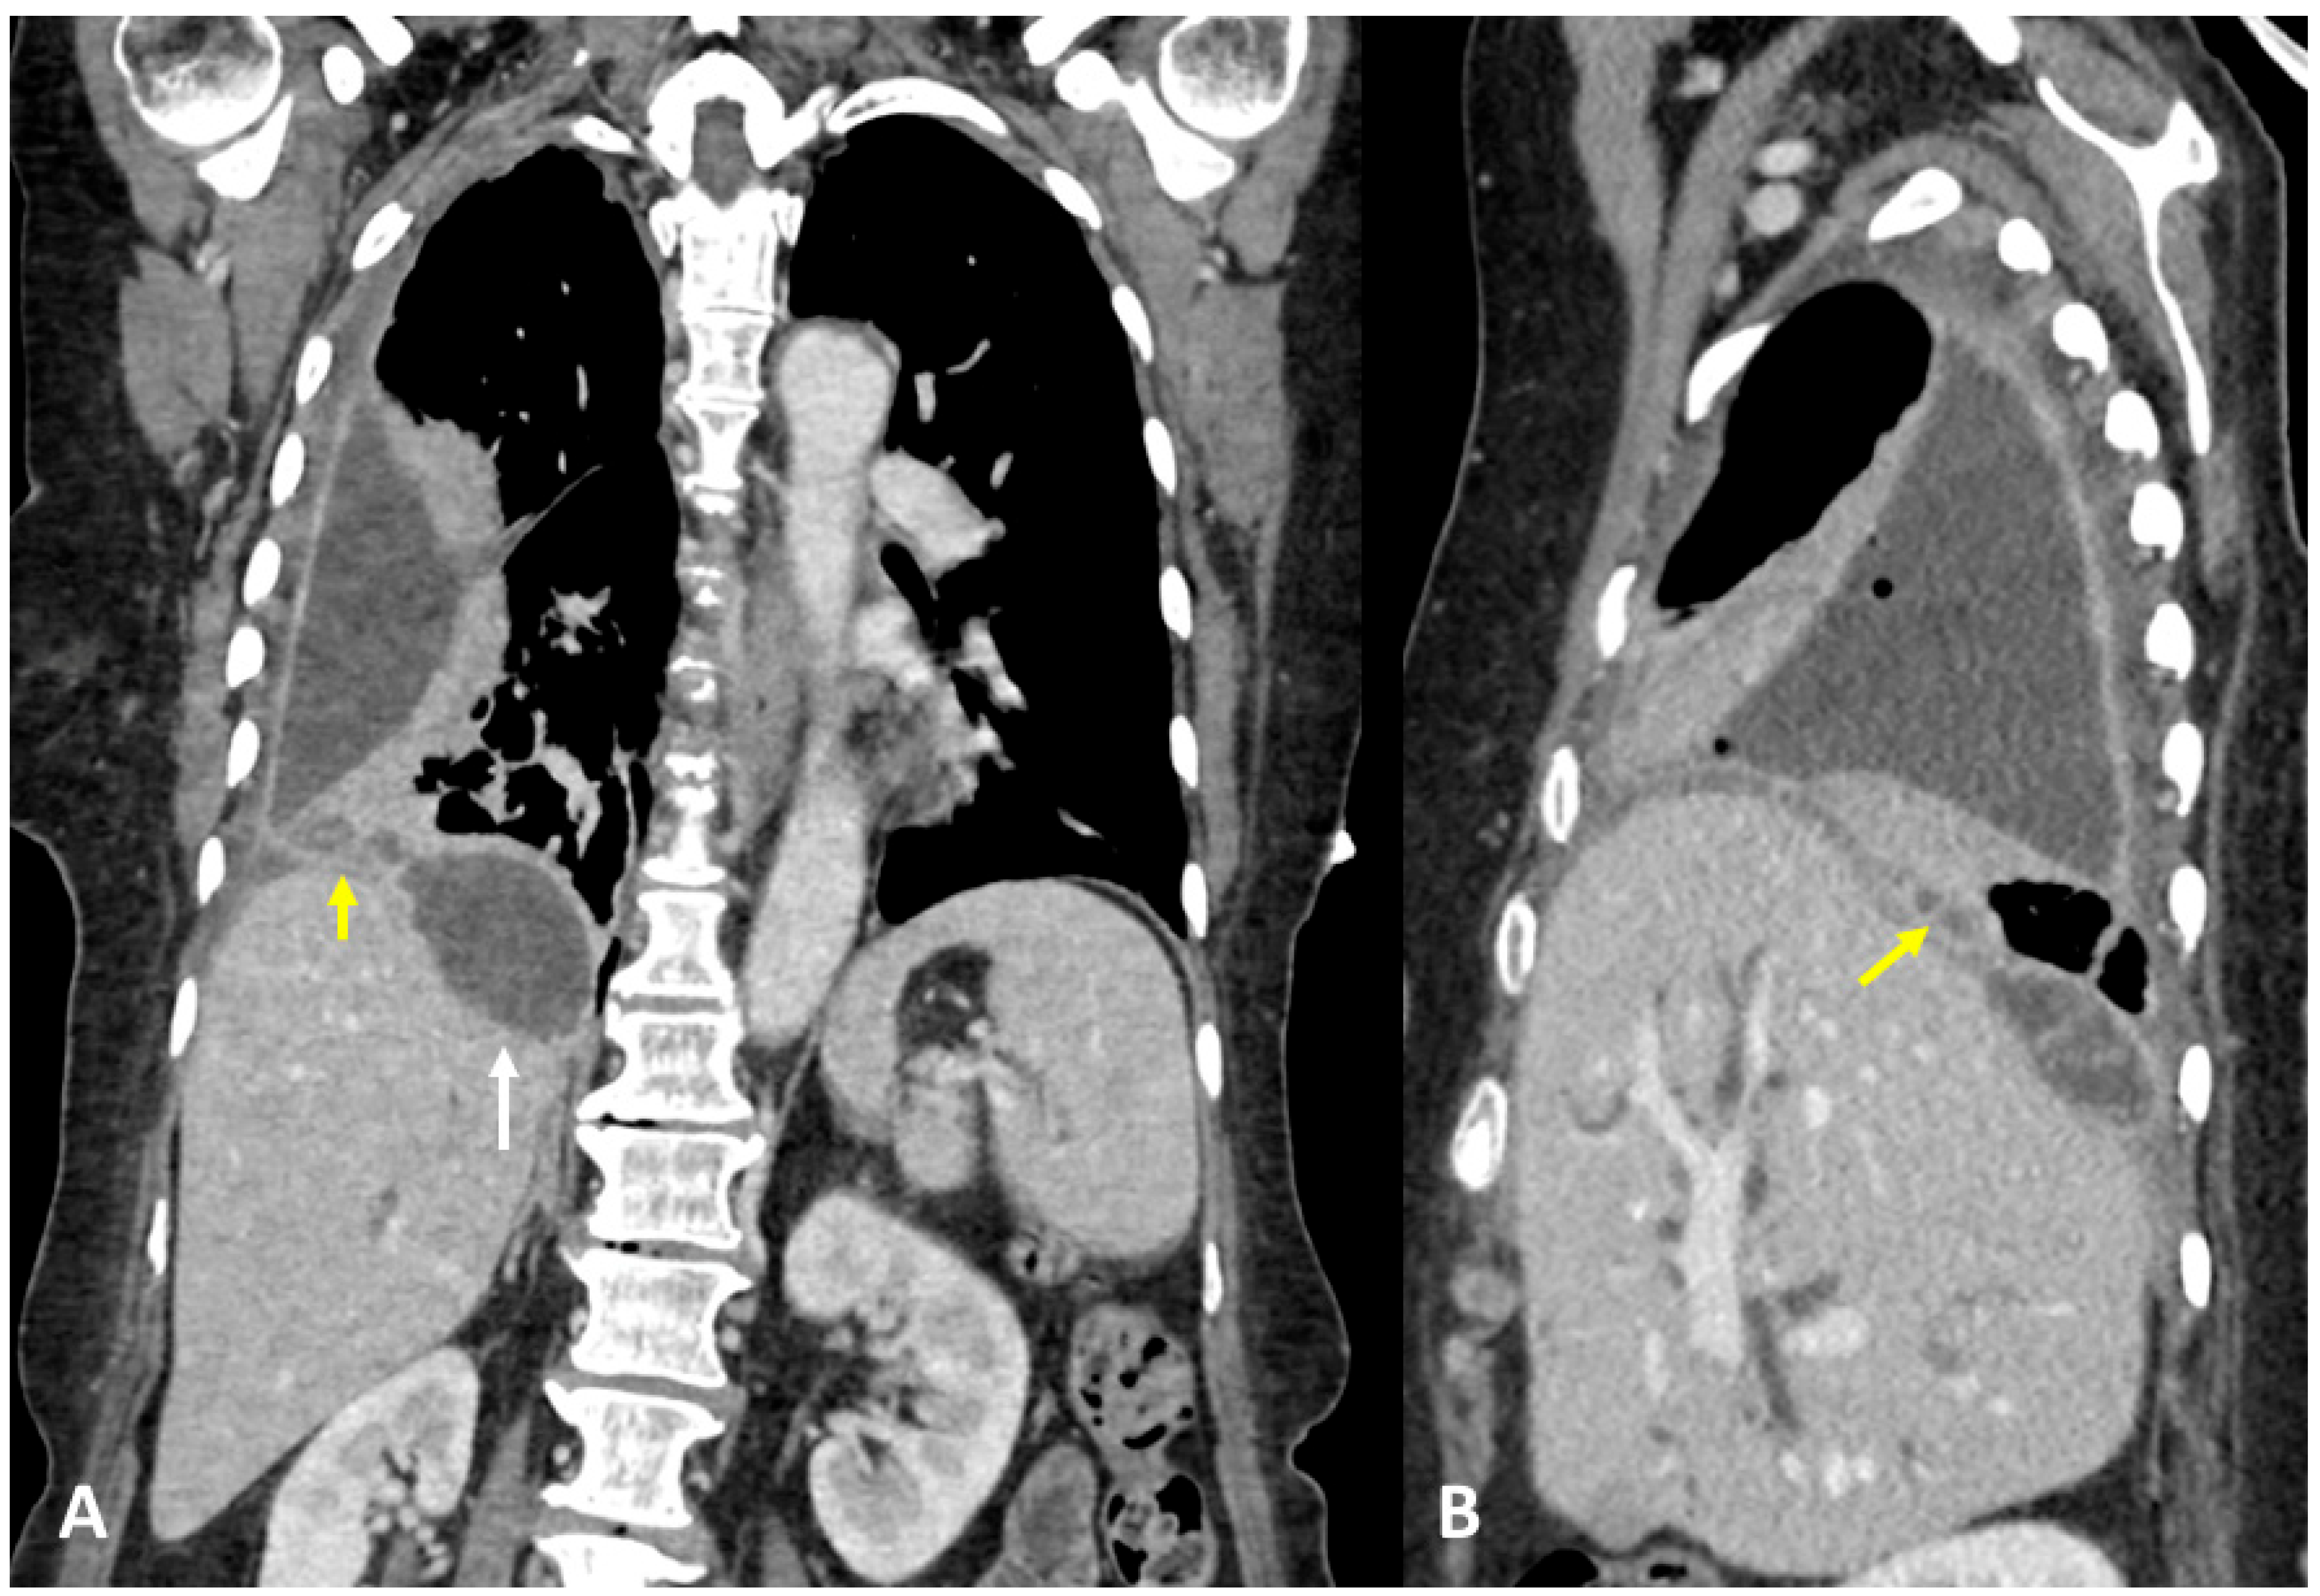

3.1. Case #1: Hepato-Thoracic Fistula

3.2. Case #2: Hepato-Thoracic Fistula

3.3. Case #3: Hepato-Thoracic Fistula

3.4. Case #4: Pancreaticopleural Fistula